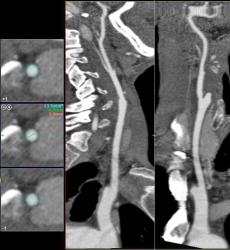

Мужчина, 62 года. Перенес ишемический инсульт в бассейне правой средней мозговой артерии.

На КТ-ангиографии выявлена окклюзия правой внутренней сонной артерии в области развилки в виде паламени свечи (красная стрелка), стеноз высокой степени в устье правой вертебральной артерии (желтая стрелка), небольшой перегиб в устье левой вертебральной артерии (голубая стрелка).

Вы отчасти правы. Инсульт пациент перенес давно, тогда не было возможности ни диагностировать, не лечить. Сейчас ему планируют установить стент в правую позвоночную артерию.

Больному успешно установлен стент в устье правой вертебральной артерии.